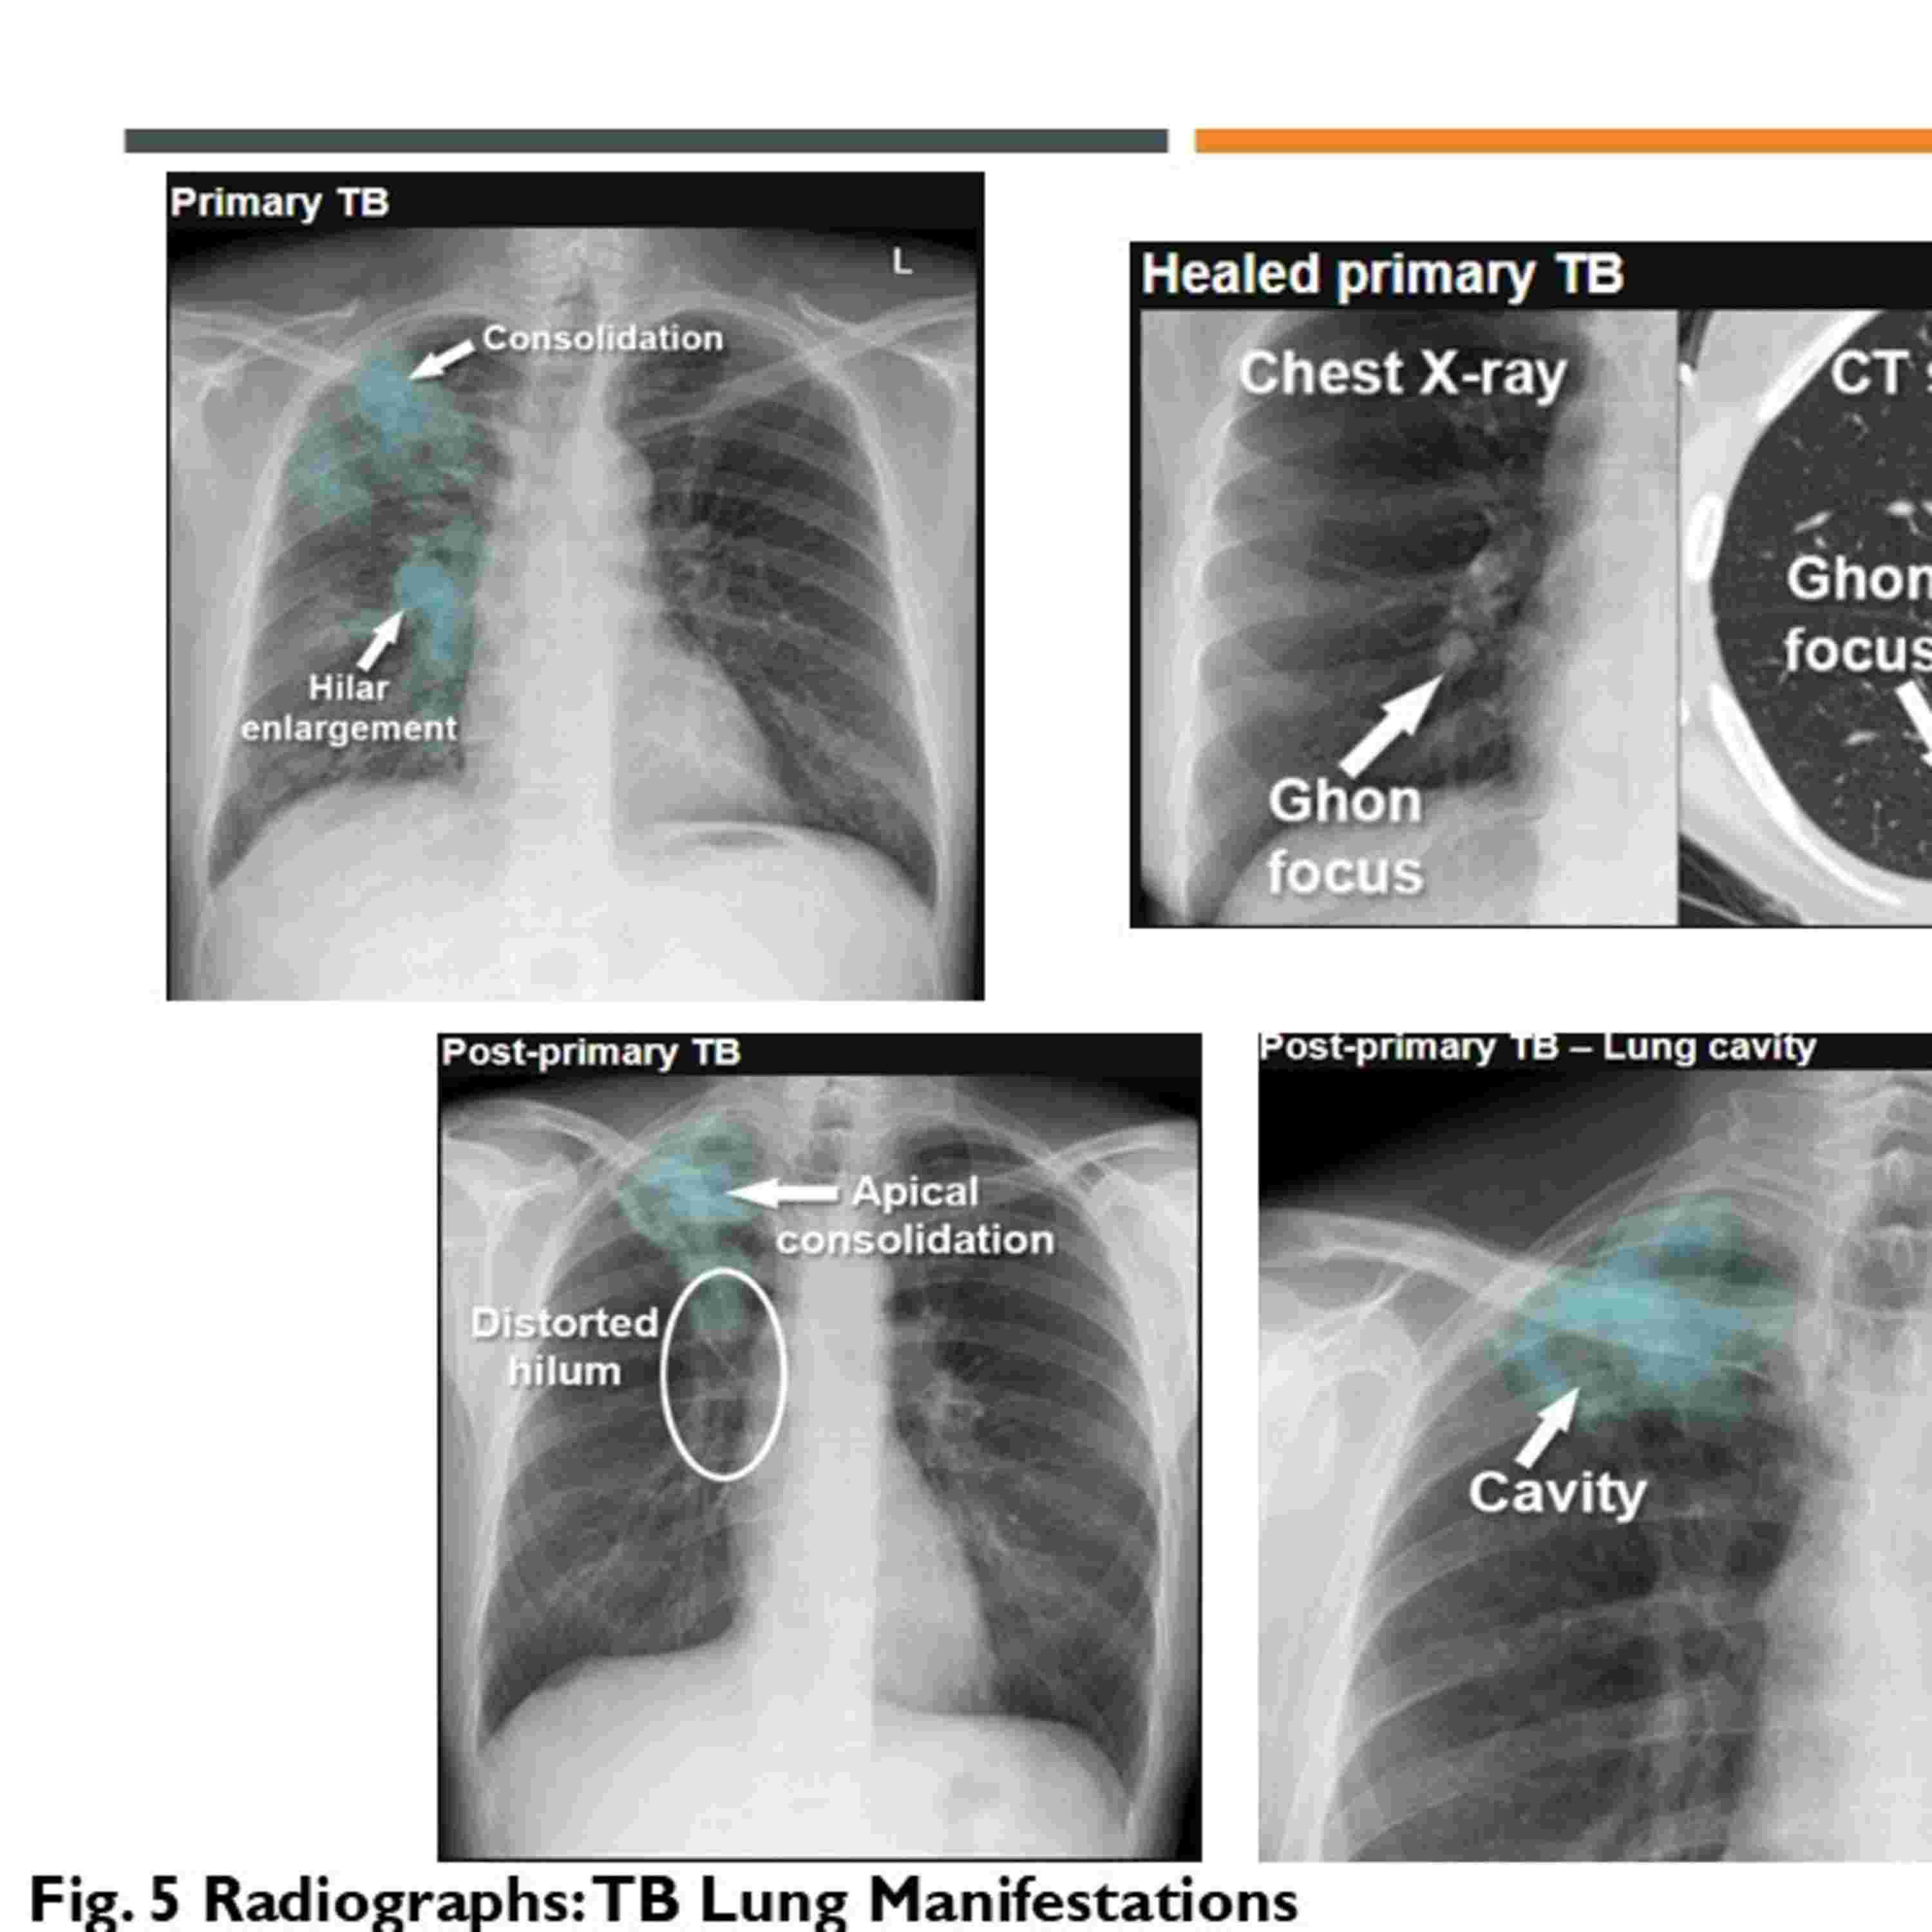

This episode is based on a presentation I delivered as part of an assessment during a clinical course in December 2023. Its on tuberculosis (TB) and covers its causative agent, transmission, global impact, and epidemiology in the UK. It details symptoms, diagnostic methods, and risk factors, while focusing on treatment management, including standard antibiotic regimens and the evolving role of video-observed therapy (VOT) as an alternative to directly observed therapy (DOT). The presentation also highlights NICE guidelines, advocating for improved detection of latent TB and streamlined treatment for active TB, and calls for further research on VOT's effectiveness.